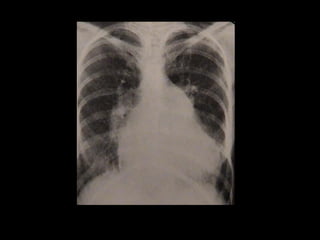

RADIOGRAFIA DE TORAX

Se crônica - aumento das câmaras esquerdas

Se agudo – congestão pulmonar

RADIOGRAFIA DE TORAX Secrônica - aumento das câmaras esquerdas Se agudo – congestão pulmonar